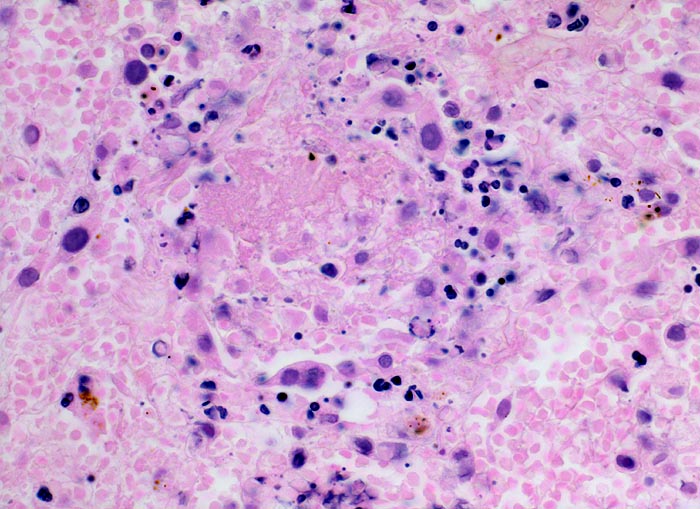

hämorrhagischer Lungeninfarkt

Das Lungengerüst ist nur noch schattenhaft erkennbar. Die Kerne von nekrotischen Typ II Pneumozyten sind stark abgeblasst. Von anderen Zellen sind nur noch Kerntrümmer erkennbar. Die Alveolen enthalten reichlich Blut und Fibrin.

Tiefe Beinvenenthrombosen bei metastasierendem Prostatakarzinom. Koronare Herzkrankheit.

400